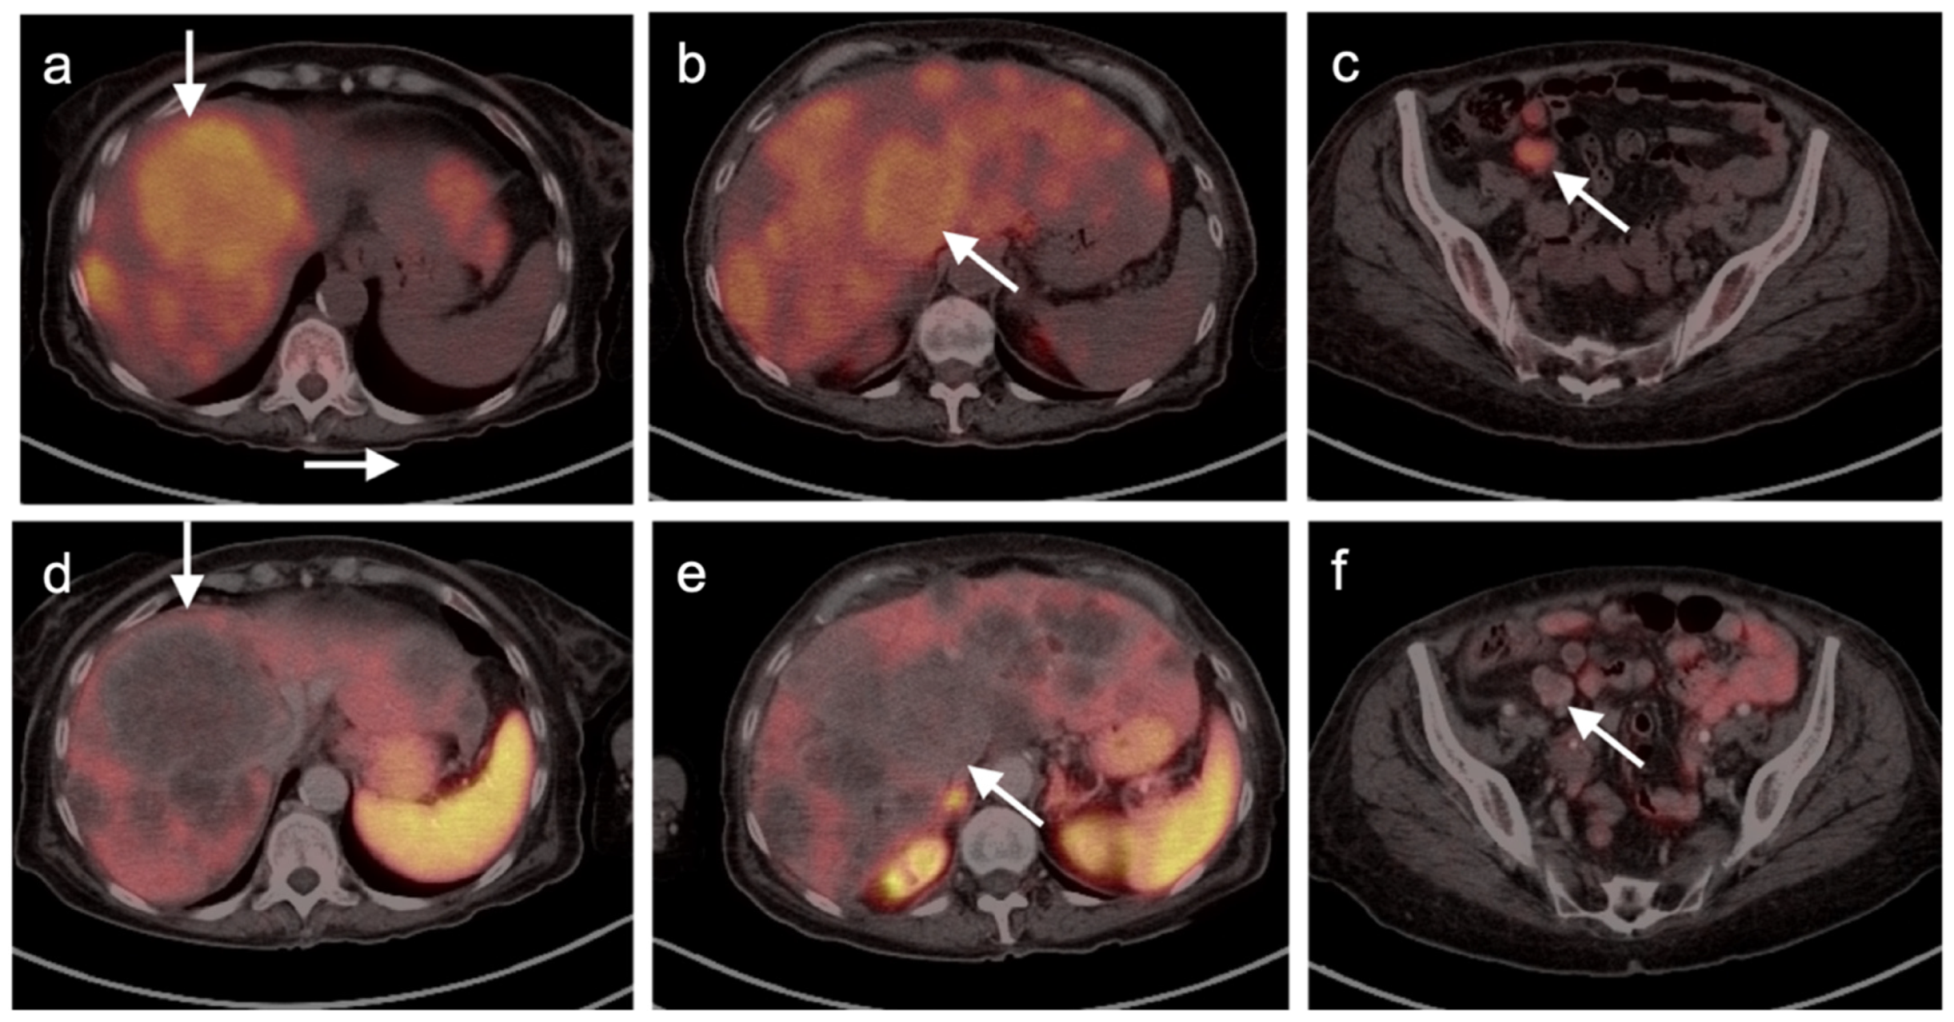

4.5. Pheochromocytoma and Paraganglioma